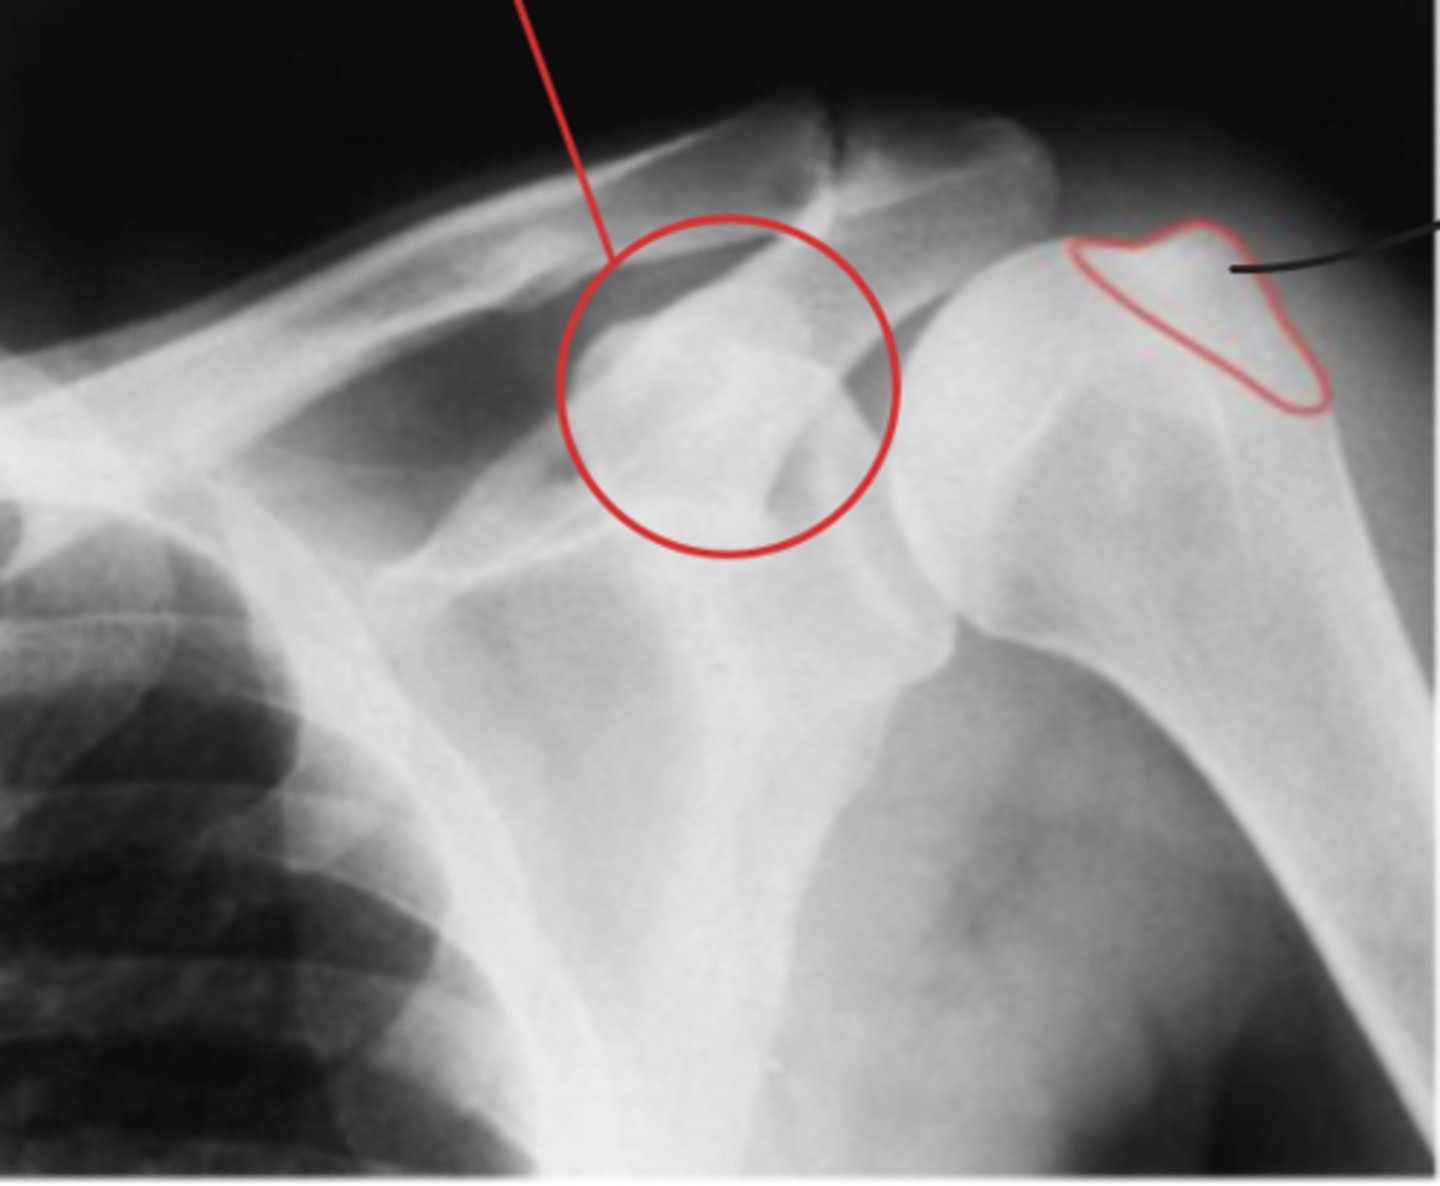

Anterior/Inferior displacement of the GHJ

What is the issue?

Hill Sachs lesion

Bankart fracture